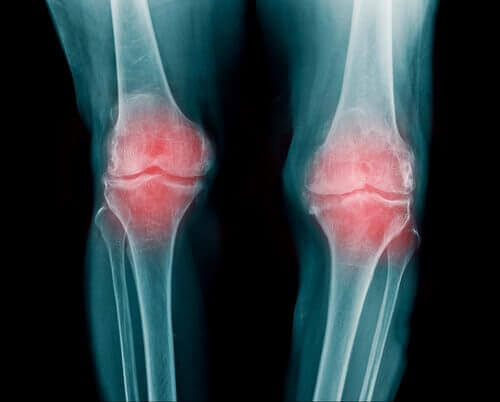

Leddene finner man på enden av beinene i kroppen din. Disse leddene har ansvaret for å beskytte kondylene dine. De har også en grunnleggende rolle i bevegelsen av øvre og nedre ekstremiteter. Imidlertid kan overbruk av dem kan forårsake ulike sykdommer. Blant dem skiller slitasjegikt seg ut. Mellom hvert ledd er et segment av brusk anordnet. Dette hindrer beinene dine fra å gnisse mot hverandre. Men tidens gang fører til gradvis reduksjon av dette brusket. Dette medfører igjen smerte og betennelse. Les om matvarer for å forhindre slitasjegikt!

Smerten som er tilstede i denne sykdommen, skyldes den inflammatoriske prosessen, og ikke at vevet tæres ned. Imidlertid er hevelse den viktigste reaksjonen på cellulær slitasje.